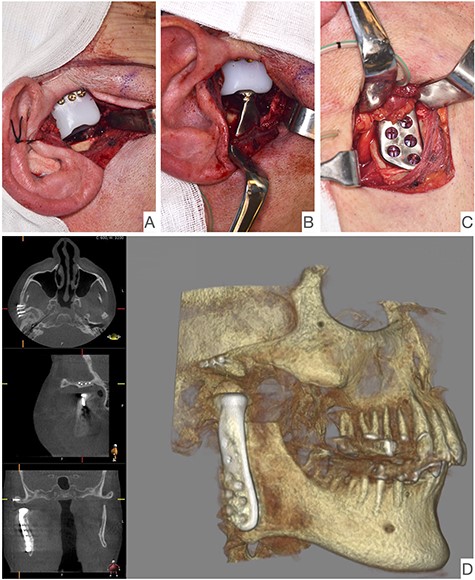

Intraoperative image showing the articular fossa (A) in combination with the articulating condylar component (B), the fixed ramus component (C) and the postoperative CBCT of the right side (D).